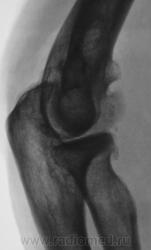

Пациент направлен на рентгенографию локтевого сустава. Была травма или не была не помнит. Пациент весьма пьющий, направлен хирургом с диагнозом "перелом". Рука в локтевом суставе полность не разгибается.

Ваше мнение уважаемые коллеги?

Наверно, застарелый перелом в области блока плечевой кости. Не понятен периостит.